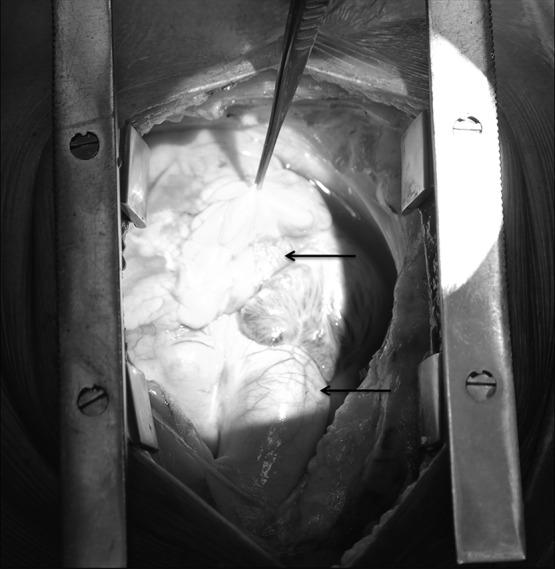

Development of coronary artery aneurysm (CAA) after implantation of drug-eluting stent is occasionally observed. We present a case of a 67-year-old man who underwent everolimus-eluting stent (EES) implantation in right coronary artery (RCA) for inferior wall myocardial infarction, and thereafter, giant CAAs were developed in the vessel of stent deployment, within 2 months. However, the patient was managed with coronary artery bypass grafting (CABG). On follow-up, the patient's condition was stable. To the best of our knowledge, we report the first case of occurrence of EES-associated giant CAAs in RCA subsequently treated with CABG.

摘要

药物洗脱支架植入后偶尔会观察到冠状动脉瘤(CAA)的发生。我们报告一例67岁男性患者,其因下壁心肌梗死在右冠状动脉(RCA)植入依维莫司洗脱支架(EES),此后在支架置入血管内2个月内出现巨大CAA。然而,该患者接受了冠状动脉旁路移植术(CABG)治疗。随访时,患者病情稳定。据我们所知,我们报告了首例RCA中发生EES相关巨大CAA并随后接受CABG治疗的病例。